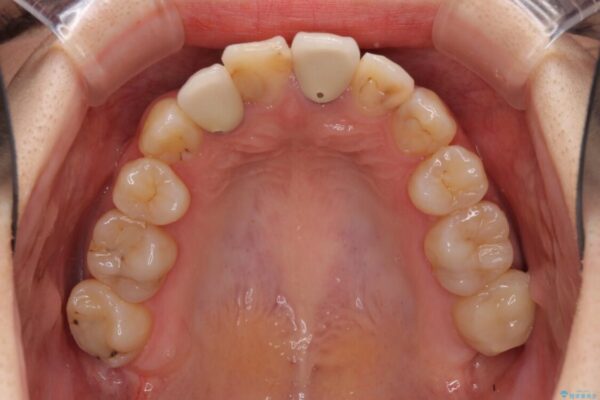

治療途中

• 虫歯治療ついでに歯並びの後戻りを改善 インビザラインによる矯正治療 治療途中画像